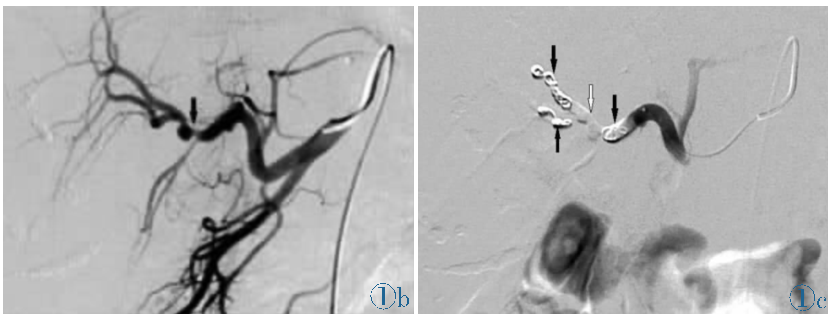

★ 病例1:十二指肠溃疡出血:超选造影发现外溢,弹簧圈联合微球栓塞成功止血

图:造影见胃十二指肠动脉近段动脉瘤,并可见造影剂溢出;弹簧圈栓塞后动脉瘤闭塞。